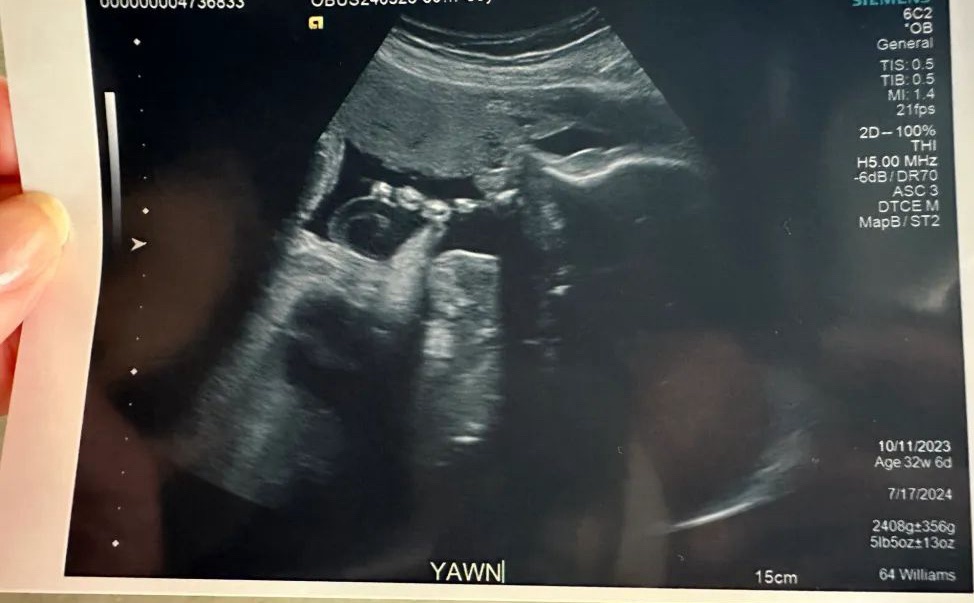

At the end of the day, I want to birth a healthy, thriving young lady; and I am well aware that there may be circumstances outside of my control that will impact how my baby comes into the world — especially given the fact that she is in the 96th percentile.